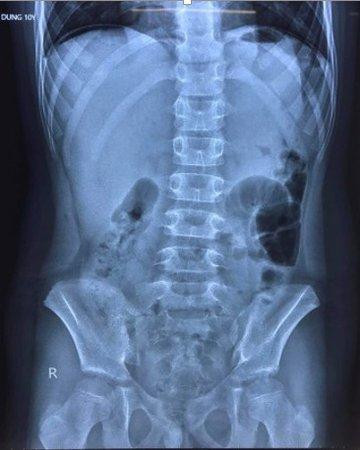

| Hình ảnh chụp X-quang cho thấy bệnh nhi có liềm hơi dưới vòm hoành 2 bên, bác sĩ nghi thủng tạng rỗng. Ảnh: Bệnh viện Trẻ em Hải Phòng cung cấp. |

Theo hình ảnh chụp X-quang, bệnh nhi có liềm hơi dưới vòm hoành 2 bên. Tại Bệnh viện Trẻ em, bé được chẩn đoán bị viêm phúc mạc do thủng dạ dày/mắc COVID-19.